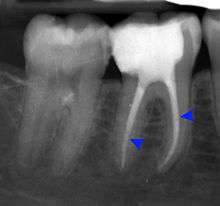

The periodontal ligament becomes inflamed and there may be pain when biting or tapping on the tooth. On an X-ray, bone resporption appears as a radiolucent area around the end of the root, although this does not manifest immediately.[9]:228 Acute apical periodontitis is characterized by well-localized, spontaneous, persistent, moderate to severe pain.[4]:125–135 The alveolar process may be tender to palpation over the roots. The tooth may be raised in the socket and feel more prominent than the adjacent teeth.[4]:125–135

- Radiographs utilized to find dental caries and bone loss laterally or at the apex.

Decay (green) with apical abscess (blue)